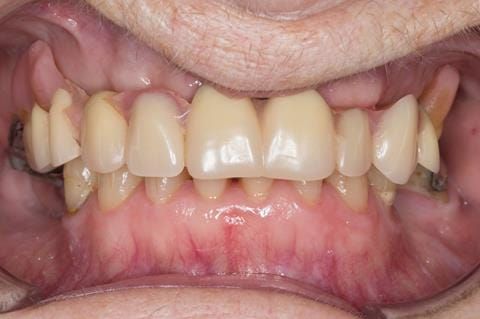

- Poorly fitting cobalt chromium based maxillary partial denture, which has been added to. This exhibited poor retention, stability and tissue fit (support). Unable to wear a new acrylic based denture.

- UR7 - occlusal amalgam. 10- 20% alveolar bone loss. Healthy periodontium with reduced attachment level. No mobility.

- Eight mandibular anterior teeth worn incisal edges from now extracted maxillary anterior crowns. Gingivitis - owing to inadequate oral hygiene.

- LL6 with large amalgam restoration - healthy periodontium.

- Bruxism.

Following consultation and second discussion appointment the patient chose to have option 2 namely, a window denture - maxillary cobalt chromium based partial denture. The clinical situation and treatment process is shown in detail below with photographs. The patient was successfully rehabilitated with this and her quality of life considerably improved. The clinical work was provided by Finlay and the technical work by Rowan.